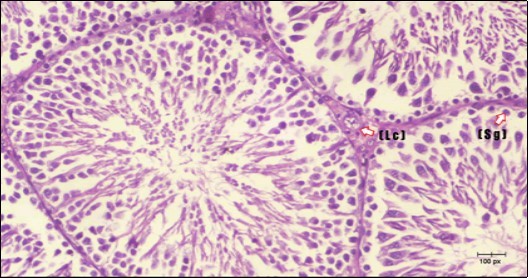

Histological examination of control rats' testis showed normal histological structure of the seminiferous tubules with an increase in the spermatogonia and other spermatocytes compared with the diabetic rats which showed an obvious decrease in the count of germinal cells generally and sloughing of germ cell in the lumen of seminiferous tubules in addition to absence of the mature sperms (Figure 3 and Figure 4). Rats tested of Fenugreek group and those treated with Glimepiride (Figure 5 and Figure 6) presented an increase in the number of spermatogenic cells and mature sperms with few focal necrotic cells. Whereas the combination therapy group showed normal histological structure of the seminiferous tubules with normal spermatogonia, presence of ledying cells and more mature of sperms (Figure 7). STZ reduced testosterone production, suggesting a decrease in the function of both Leydig (testosterone producing cell) and Sertoli (spermatogenesis) cells, which might be caused by a reduction in insulin secretion. These changes are probably due to increased Reactive Oxygen Species (ROS) production by accelerated Advanced Glycation End Products (AGE) formation 31 hexosamine and Protein Kinase C pathway. The administration of Fenugreek seeds to diabetic rats significantly decrease of sperm shape abnormality and improve the sperm count 32. Glimepiride reduced sperm abnormality and increased testis weights and sperm count by its antioxidant action 30. The potential protective efficacy of Fenugreek seed extract when added to Glimepiride was observed on reproductive systems.

Figure 3.Photomicrogragh of testis section of a control rat showing testicular tissue with seminiferous tubules separated by interstitial tissue with Ledying cells (arrow). Seminiferous tubules with complete spermatogenesis, Sertoli cell (dashed-arrow) and spermatozoa . (H&E) (40X).

Figure 5.Photomicrogragh of testis section of treated rat with Fenugreek showing noticeable improvement with increased number of spermatogenic cells included moderate amount of spermatozoa (star) and organized Sertoli cells (arrow). Note liquid infiltration (dashed arrow) in wide interstitial tissue (H&E) (40x).